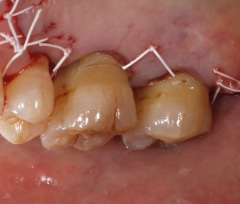

| 歯茎にプラーク(歯垢着が)と歯石の沈認められます。歯肉が腫れ、出血がありました。 | 歯科衛生士の治療と、ブラッシング技術の向上により、歯茎が引き締まり健康的な状態になりました。 | |

外科手術(中等度・重度歯周病の治療)

| 歯周病が進行したケースでは盲目下でポケット内の歯石を確実に除去するには限界があります。 | 局所麻酔をした後、歯茎を切開し、明視下にて歯根面の歯石や炎症組織を取り除き、歯周ポケットの除去をおこないました。 |